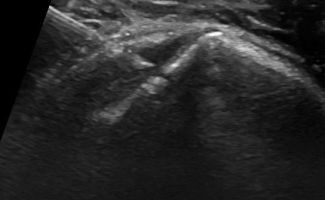

Η τεχνική PRP περιλαμβάνει τη λήψη μίας μικρής ποσότητας αίματος του ασθενούς, το οποίο φυγοκεντρείται ώστε να διαχωριστεί το πλάσμα που είναι πλούσιο σε αιμοπετάλια. Το προκύπτον πλάσμα εγχέεται, με την καθοδήγηση υπερήχου, στο σημείο της βλάβης.

Η καθοδήγηση υπερήχου κατά την ενέσιμη θεραπεία PRP αποτελεί κρίσιμο παράγοντα για την ακρίβεια και ασφάλεια της διαδικασίας.

Με τη δυνατότητα παρακολούθησης της βελόνας σε πραγματικό χρόνο, εξειδικευμένος Ιατρός-Ακτινολόγος μπορούν να καθορίσει με απόλυτη ακρίβεια την περιοχή όπου πρέπει να γίνει η ένεση. Αυτό εξασφαλίζει ότι η εισαγωγή του PRP θα γίνει ακριβώς στην επιθυμητή θέση, αποφεύγοντας γύρω ιστούς, νεύρα και αιμοφόρα αγγεία.

Η χρήση της υπερηχογραφίας όχι μόνο μειώνει τον κίνδυνο επιπλοκών, αλλά βελτιώνει και τα αποτελέσματα της θεραπείας, καθώς η ένεση διενεργείται με ακρίβεια στην πάσχουσα περιοχή, και όχι κατά προσέγγιση.